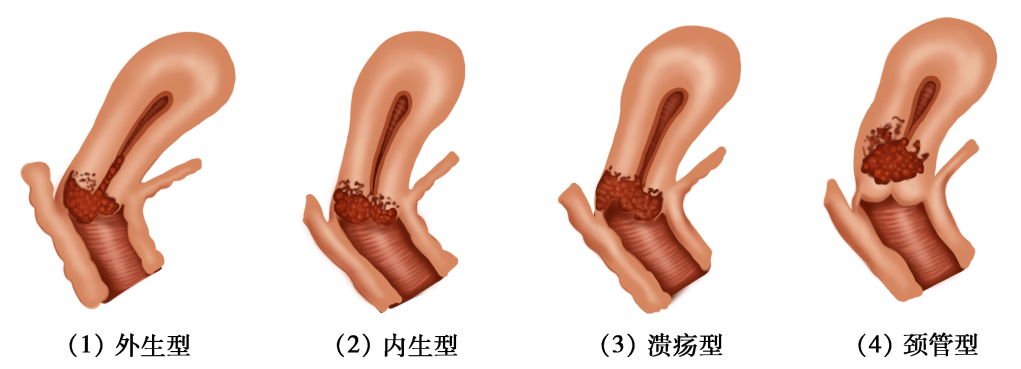

(1)巨检:微小浸润性鳞状细胞癌肉眼观察无明显异常,或类似子宫颈柱状上皮异位。随病变发展,可形成4种类型(图25-5)。

图25-5 子宫颈癌类型(巨检)

1)外生型:最常见,癌灶向外生长呈乳头状或菜花样,组织脆,触之易出血。常累及阴道。

2)内生型:癌灶向子宫颈深部组织浸润,子宫颈表面光滑或仅有柱状上皮异位,子宫颈肥大变硬,呈桶状。常累及宫旁组织。

3)溃疡型:上述两型癌组织继发展合并感染坏死,脱落后形成溃疡或空洞,似火山口状。

4)颈管型:癌灶发生于子宫颈管内,常侵人子宫颈管和子宫峡部供血层及转移至盆腔淋巴结。